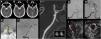

La «Cone-Beam computed tomography» (CBCT) o tomografía computarizada de haz cónico obtiene imágenes tridimensionales mediante un detector bidimensional. Su aplicación en la planificación y evaluación de los procedimientos mínimamente invasivos guiados por imagen, puede mejorar tanto la seguridad como la eficacia de intervenciones vasculares y percutáneas. El objetivo de este manuscrito es hacer una revisión de las consideraciones técnicas, de las principales aplicaciones clínicas y direcciones futuras de la CBCT en radiología vascular e intervencionista y en neurorradiología intervencionista.

Cone-Beam computed tomography (CBCT) obtains three-dimensional images using a two-dimensional detector. The use of CBCT in treatment planning and evaluation increases the safety and efficacy of minimally invasive procedures. This article reviews the technical considerations, main clinical applications, and future directions of CBCT in vascular and interventional radiology and interventional neuroradiology.